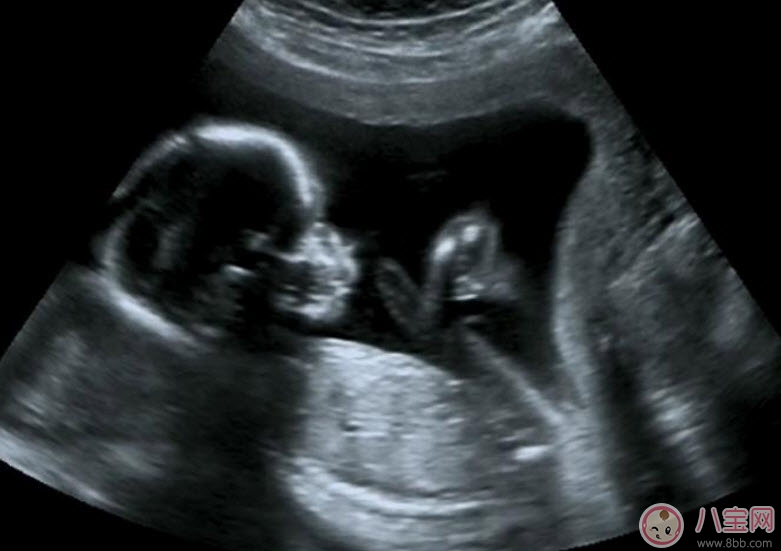

為監(jiān)測孕囊的部位、胎兒的生長發(fā)育情況,降低畸形兒和有缺陷兒的出生率,早孕期陰道B超檢查顯然是很必要的。早孕期做陰道B超檢查有以下幾點(diǎn)好處:

1.清楚地了解孕囊的位置是否正常,明確是宮內(nèi)還是宮外妊娠(俗稱宮外孕)。

2.核實(shí)孕周、判斷胚胎發(fā)育情況。根據(jù)孕囊的平均直徑、胎芽大小、胎兒的頭臀長判斷孕齡,有助于中晚孕期間判斷胎兒發(fā)育的狀況。經(jīng)陰道B超胎芽大于5mm時(shí),應(yīng)該見到胎心搏動(dòng)。如果沒有見到胎心搏動(dòng),提示有胚胎停止發(fā)育 的可能,應(yīng)定期復(fù)查。

3.判斷胚胎的數(shù)目,這是早期診斷是否多胎妊娠的最準(zhǔn)確的方法。

4.觀察胎盤的早期發(fā)育。妊娠6周時(shí),胚胎的葉狀絨毛膜與子宮的底蛻膜開始形成原始胎盤,妊娠8周,就可以辨認(rèn)出胎盤了。

5.及早發(fā)現(xiàn)子宮、附件的異常。了解是否有子宮畸形、肌瘤以及附件區(qū)腫物等等。